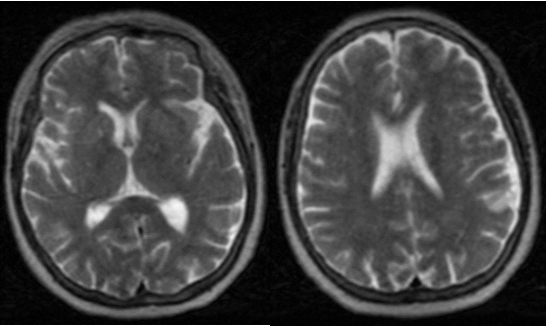

Figure 3 MRI of the brain without lesions FLAIR axial, sagittal, sagital.

Figure 4 T 2 brain MRI.

MRI has limited specificity for diagnosis, as well as for prognosis even though other neurological pathologies can be excluded. The axial and sagittal Flair images can be visualized in the MRI, as well as in the T2 images, there is no evidence of lesions in the cerebral parenchyma.